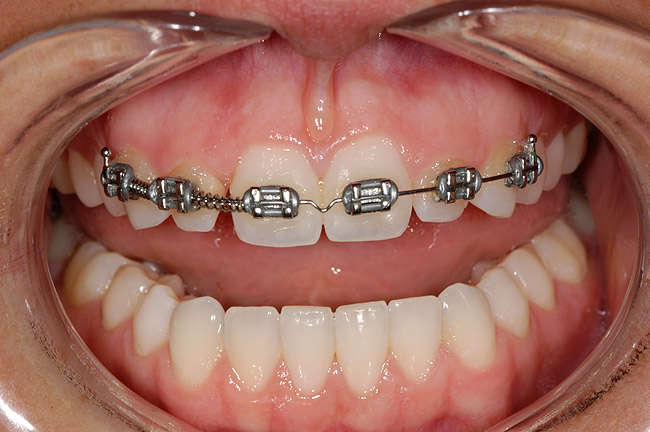

Figure 3 Additional orthodontic treatment is initiated to improve the dental midline and evenly distribute the space around the microdontic lateral incisors.

Figure 3

Figure 4 The dental midline is in improved harmony with the facial midline following the second round of orthodontic treatment.

Figure 4